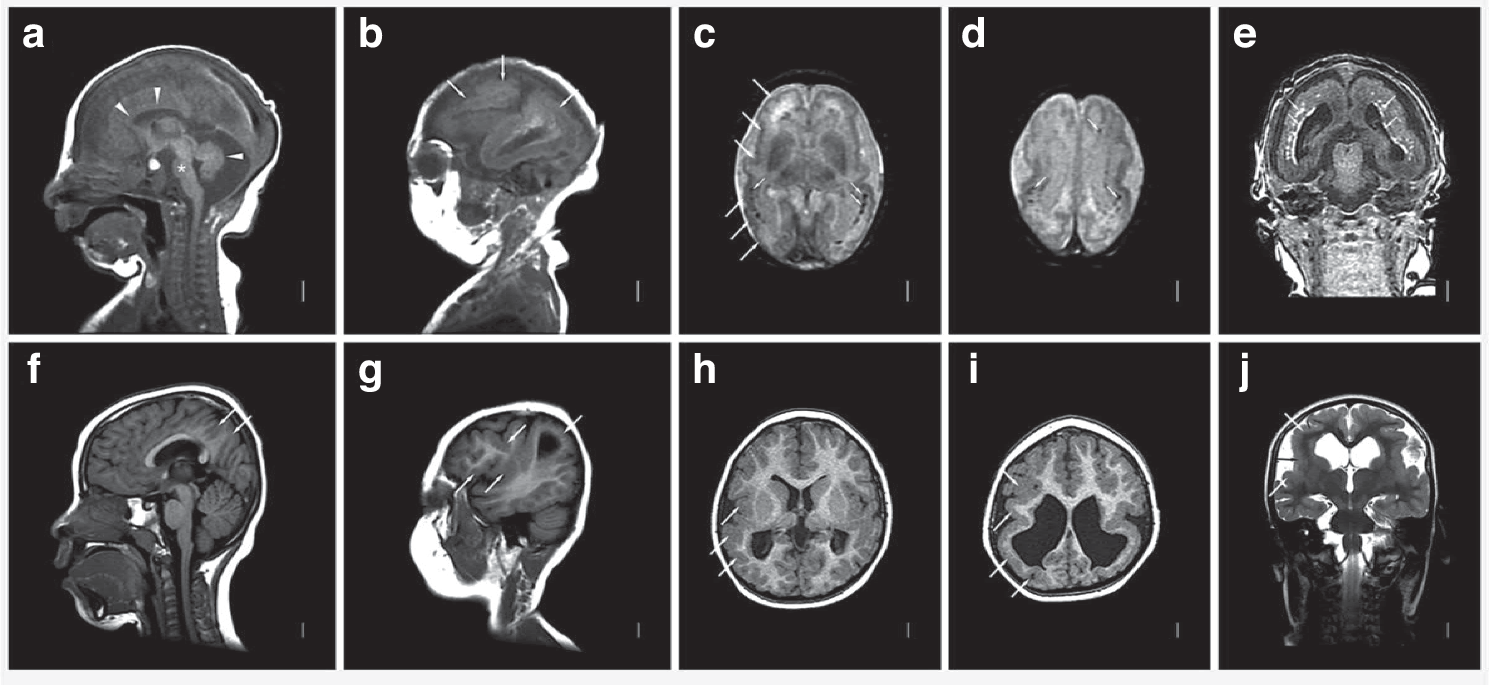

Fig. 1: MRI scan findings in CACMV.

This image demonstrates brain MRI abnormalities observed in cCMV. Images from a child with CACMV (panels a–e) demonstrate diffuse thin corpus callosum (upper arrowheads in a), small pons (asterisk in a), diffuse cerebellar hypoplasia (lower arrowhead in a), diffuse reduced number and complexity of gyri and irregular cortex consistent with PMG seen in all regions (arrows in b, long white arrows shown only on the right in c), and extensive periventricular and subcortical white matter injury and calcifications (short white arrow in c–e), and mild-moderate ventriculomegaly. Images from another patient with CACMV show normal corpus callosum and cerebellum with PMG over the parietal convexity and right perisylvian region (arrows in f, g), bilateral perisylvian predominant PMG (long white arrow shown only on the right in (h–j), and moderate posterior ventriculomegaly. The images include T1-weighted sagittal (a, b, f, g), T2-weighted non-turbo axial (c, d), 3D-MPRAGE coronal (e) and axial (h, i) and T2-weighted coronal (j) sequences.